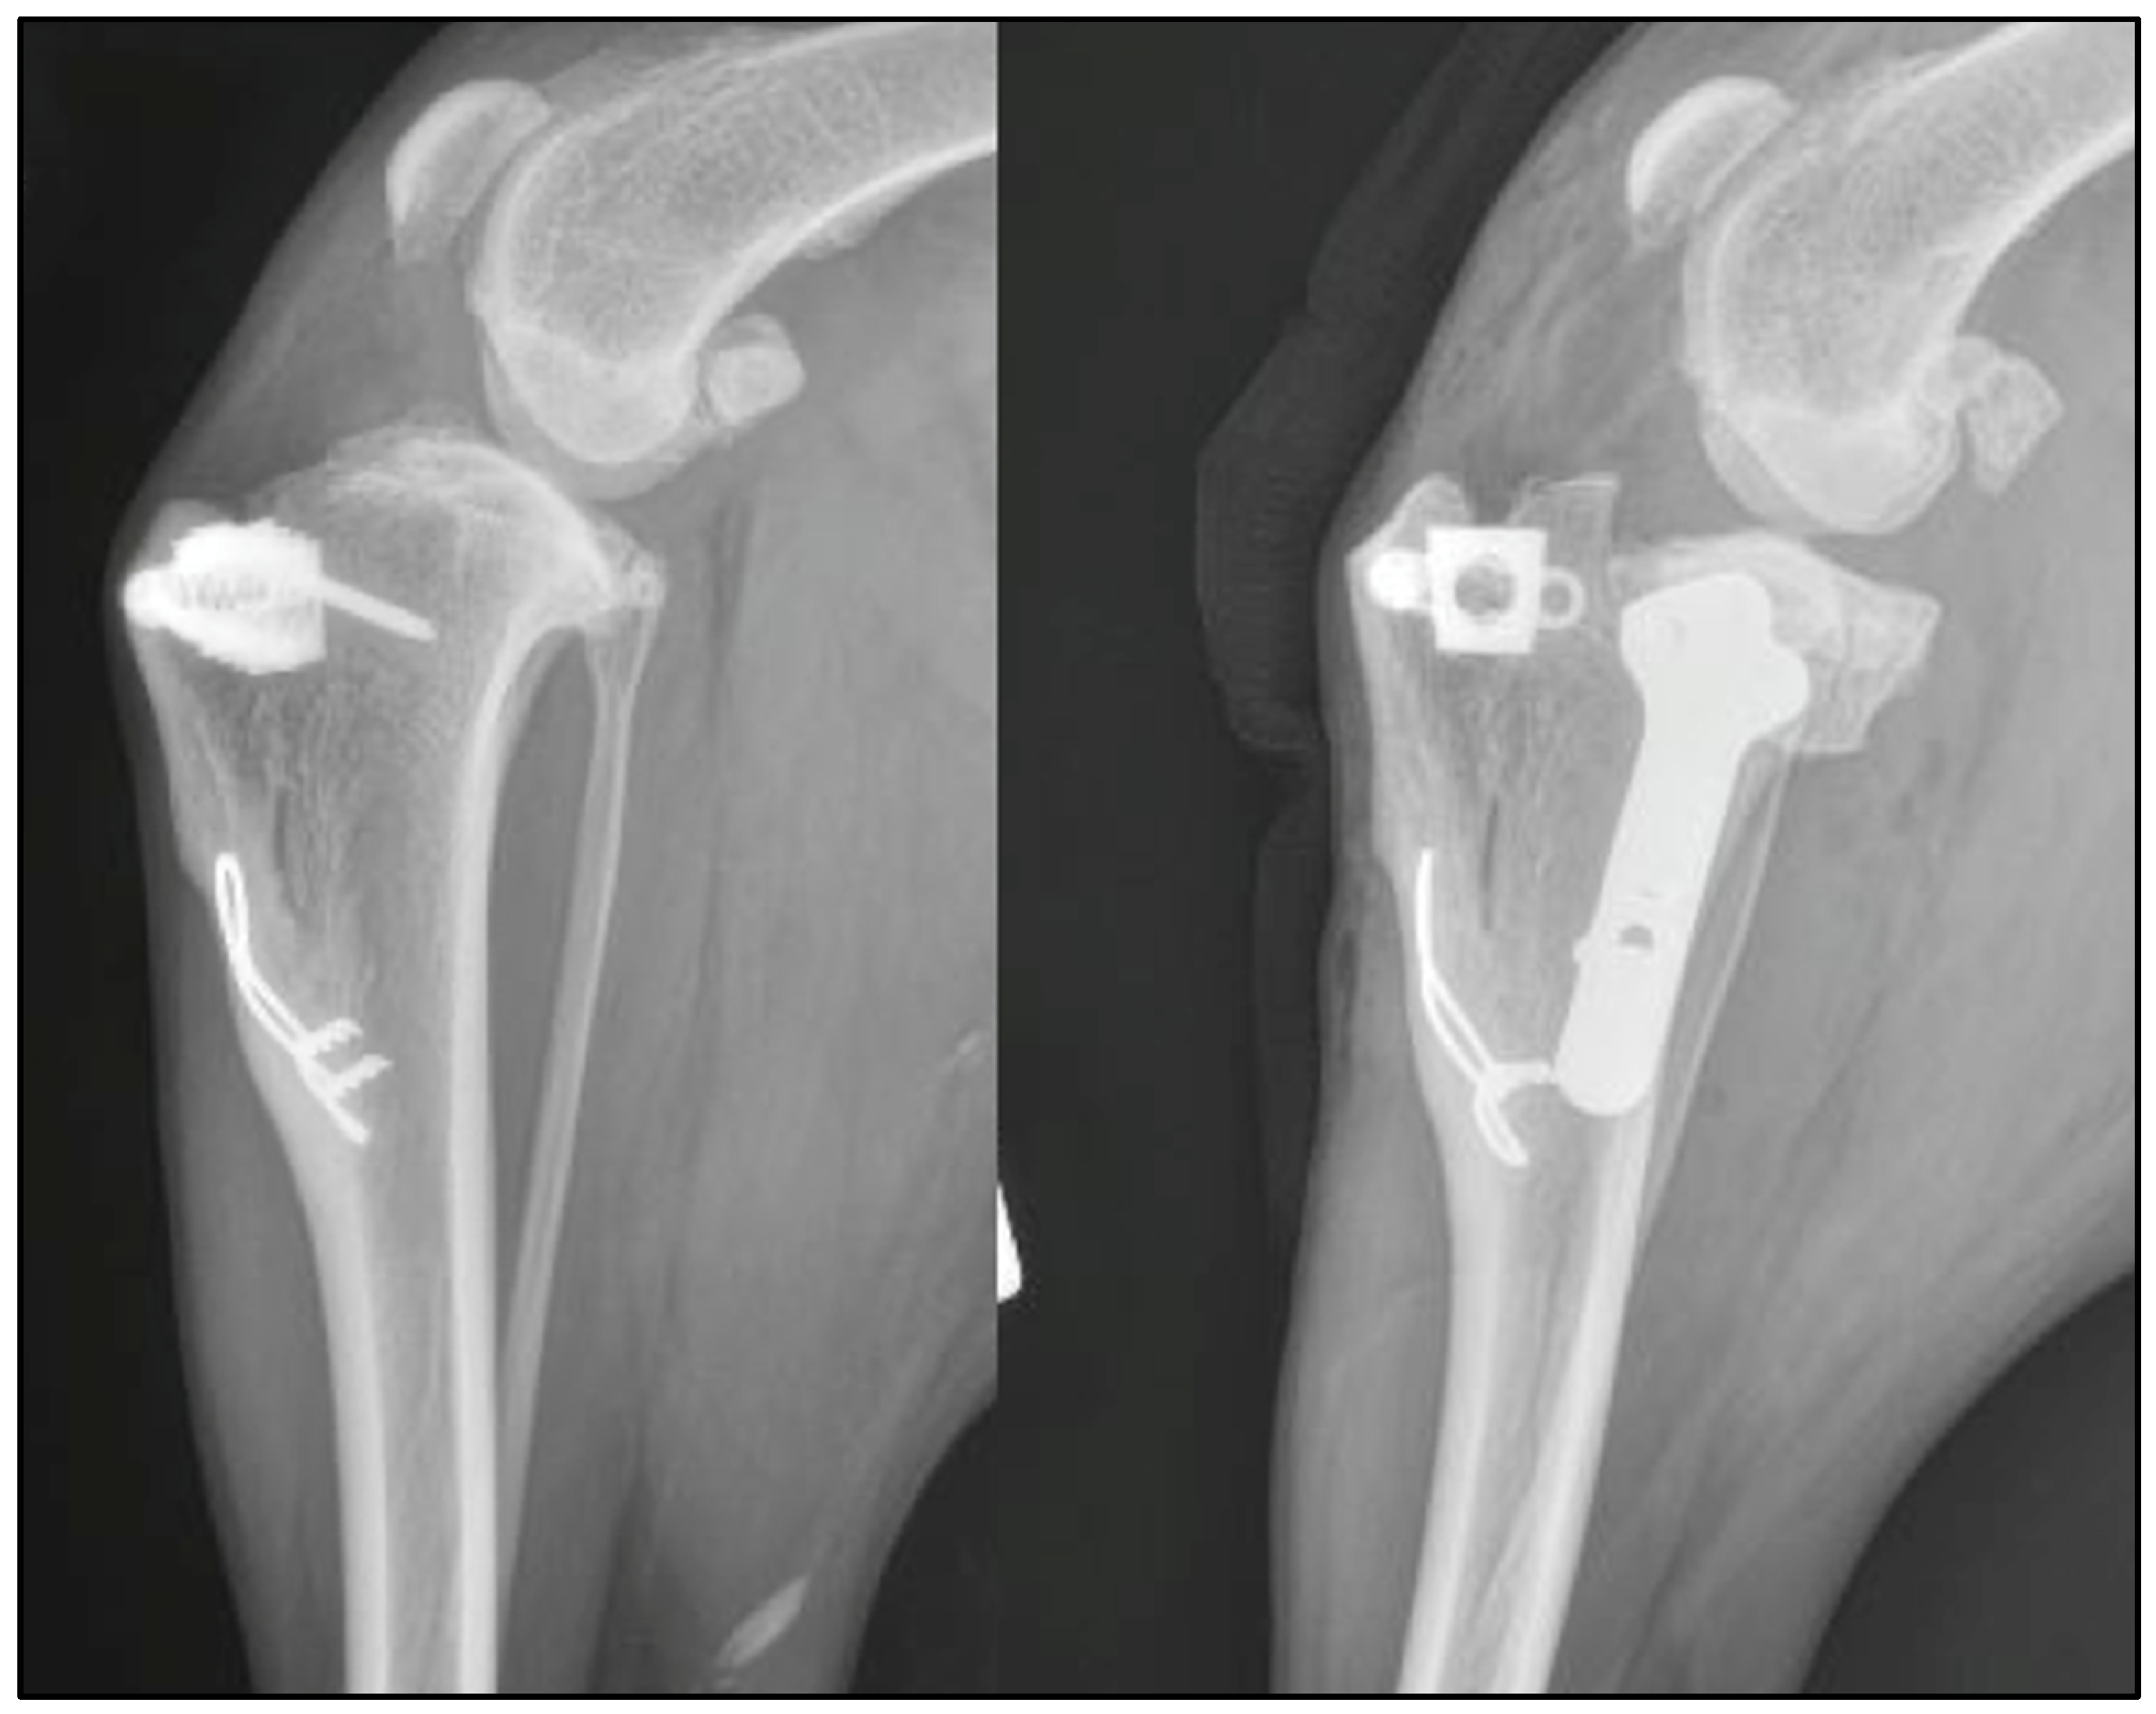

| 1 | Modified Maquet tibial tuberosity advancement | 104° | 94 ° | 28° | TPLO | Complete CCL rupture, intact menisci | 109° | 77° | 9° |

| 2 | TTA rapid | 112° | 96° | 32° | Modified CCWO (mCCWO) | Complete CCL rupture and medial meniscal tear (caudal horn) | 129° | 87° | 0° |

| 3 | Modified Maquet Procedure (MMP) | 104° | 90° | 24° | TPLO | Partial CCL rupture and intact menisci | 105° | 74° | 4° |

| 4 | MMP | 108° | 96° | 26° | TPLO and tension band | N/A | 106° | 86° | 9° |

| 5 | MMP | 137° | 102° | 34° | TPLO and tension band | N/A | 117 ° | 79° | 4° |

| 6 | MMP with 2 staples | 111° | 95° | 27° | TPLO | N/A | 115° | 79° | 8° |

| 7 | Modified Maquet Technique (MMT) | 108° | 83° | 22° | TPLO | Complete CCL rupture and medial meniscal tear (cranial horn) | 127° | 70° | 1° |